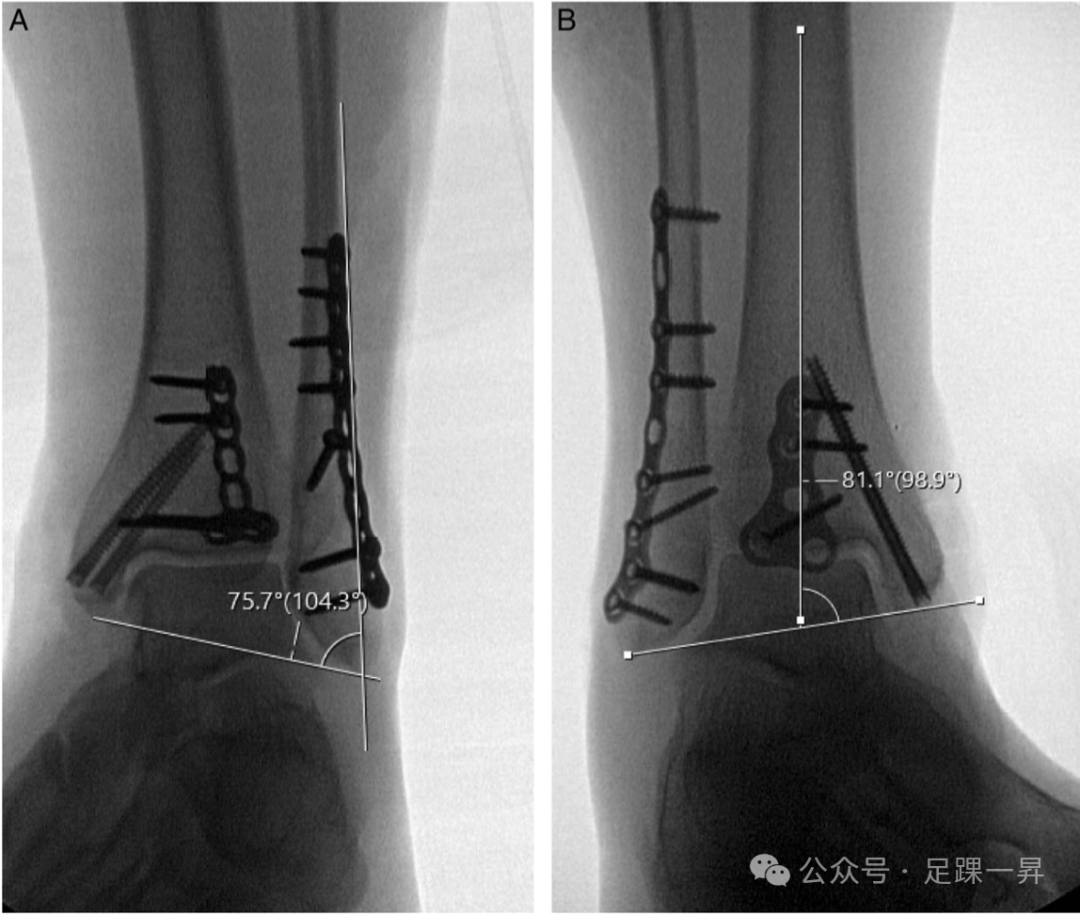

已提出若干放射学标志作为评估解剖对线的参考点,尤其在可能发生腓骨短缩的情况下。双踝角和胫距角是两个评估腓骨长度的放射学参数,需与对侧未受伤踝关节对比以评估其意义。双踝角(正常范围:72-86 度)由腓骨平行线与踝间线的夹角定义;胫距角(正常范围:75-86 度)由垂直于胫骨远端关节面的线与踝间线的交点形成。已观察到异常腓骨短缩与角度差异呈近似线性相关,1 度角度差异对应约 1 mm 短缩。

图2. A. 双踝角(正常范围:72至86度)由平行于腓骨的直线与踝间线之间的夹角定义。B. 胫距角(正常范围:75至86度)由垂直于胫骨远端关节面的直线与踝间线的交点形成。